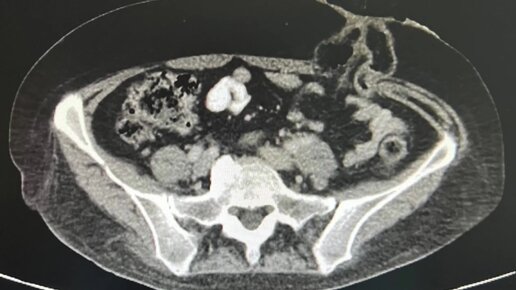

Выведенная колостома (сигмастома) при лечении рака ректосигмоидного отдела толстой кишки